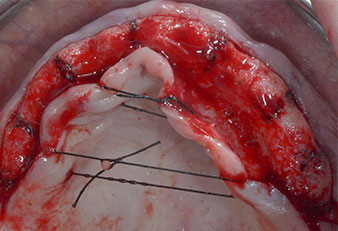

Fig. 1: Pre-operative view of the maxillary ridge, with implant positions marked with the aid of a surgical plastic template. Due to the low ridge super short posterior implants are planned.

Implant positions

Fig. 2: After mid-crestal incision and preparation of mucoperiosteal flaps the implant positions are transferred to the bone.